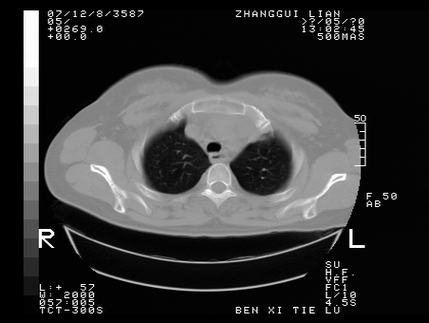

标题: CT10818:男,73,TB病史,现病史肺炎及直肠CANCER术后 [打印本页]

标题: CT10818:男,73,TB病史,现病史肺炎及直肠CANCER术后

这个请版主删除掉,这个病例我发过的,发重了,此人病史是,f,46y,胸疼,无其他原因就诊

左侧中央型肺癌伴阻塞性肺炎\\不张,左侧前上纵隔亦增宽,建议上传纵隔窗除外淋巴结转移.

考虑:左侧中央型肺癌伴阻塞性肺炎,纵隔淋巴结转移。

1)考虑为:左侧中央型肺癌伴阻塞性肺炎,纵隔淋巴结转移。2)双侧少量胸腔积液。3)心包积液。

左侧中央型肺癌伴阻塞性肺炎,纵隔淋巴结转移。

考虑左侧中央型肺癌伴阻塞性肺炎,纵隔淋巴结转移。